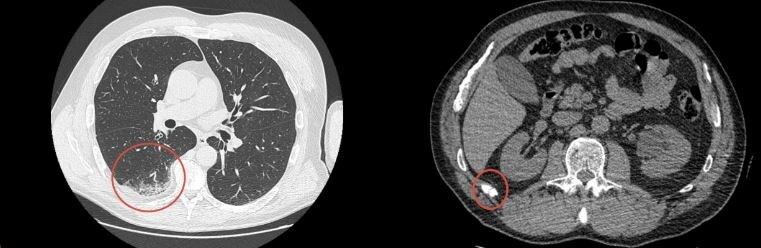

За сутки до обращения в Ильинскую больницу появилась локальная боль в грудной клетке, чётко усиливающаяся при глубоком вдохе. С учётом механизма травмы выполнена компьютерная томография органов грудной клетки, по данным которой выявлены перелом XII ребра и очаг ушиба лёгкого.

Отсроченное появление боли при травмах грудной клетки — распространённая клиническая ситуация. В первые дни после травмы болевой синдром может быть минимальным за счёт компенсаторного ограничения дыхательных движений, перераспределения нагрузки и фокуса пациента на более выраженную боль в другой зоне повреждения, в данном случае — в области плеча. По мере нарастания локального воспалительного ответа, отёка мягких тканей и микрокровоизлияний в зоне перелома и ушиба лёгкого болевой синдром становится более выраженным и клинически значимым.